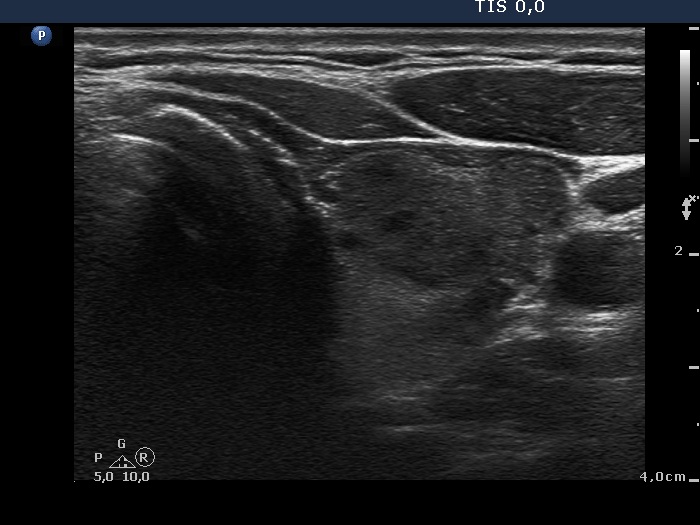

Study on 100 consecutive patients with thyroid nodule - case 001

Three years after the first examination (ultrasonographic picture 5)

Lower part of the left lobe, transverse scan. Two or three minimally hypoehogenic lesions can be found in the ventral part of this section.